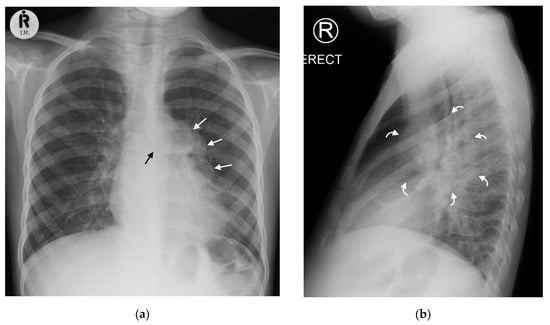

Figure 2. (a,b): Left hilar lymphadenopathy on the PA and lateral chest radiographs. (a) PA erect chest radiograph in this child with later confirmed pulmonary TB demonstrates a multilobulated lymph node mass projecting beyond the cardiac margin on the left (white arrows) consistent with left hilar lymphadenopathy. There is also loss of the left cardiac margin consistent with lingula air-space disease/atelectasis as a consequence of left main bronchus compression (black arrow). (b) Lateral chest radiograph confirms the presence of hilar lymphadenopathy by demonstrating an oval mass consistent with the ‘doughnut sign’ (curved white arrows), representing lymphadenopathy inferiorly and likely the normal vessels (aortic arch and left main pulmonary artery) superiorly.

Right hilar adenopathy (a lobulated hilar opacity on chest radiograph) obscuring the hilar point, Figure 1, is more commonly observed than left, with left hilar nodes only evident when extending beyond the left cardiac border [27]. Paratracheal adenopathy may be difficult to distinguish from other mediastinal tissues, such as the thymus, but will extend beyond the normal mediastinal contours, and may result in airway compression and deviation [27]. Left paratracheal lymphadenopathy is rarely observed in isolation, most commonly co-existing alongside other regions of mediastinal lymphadenopathy [27]. Sub- or retro-carinal lymphadenopathy is typically seen on the lateral projection as lobulated densities inferior and posterior to the bronchus intermedius, which, in combination with the more superior aortic arch and pulmonary arteries result in the well described “doughnut sign” (Figure 2).